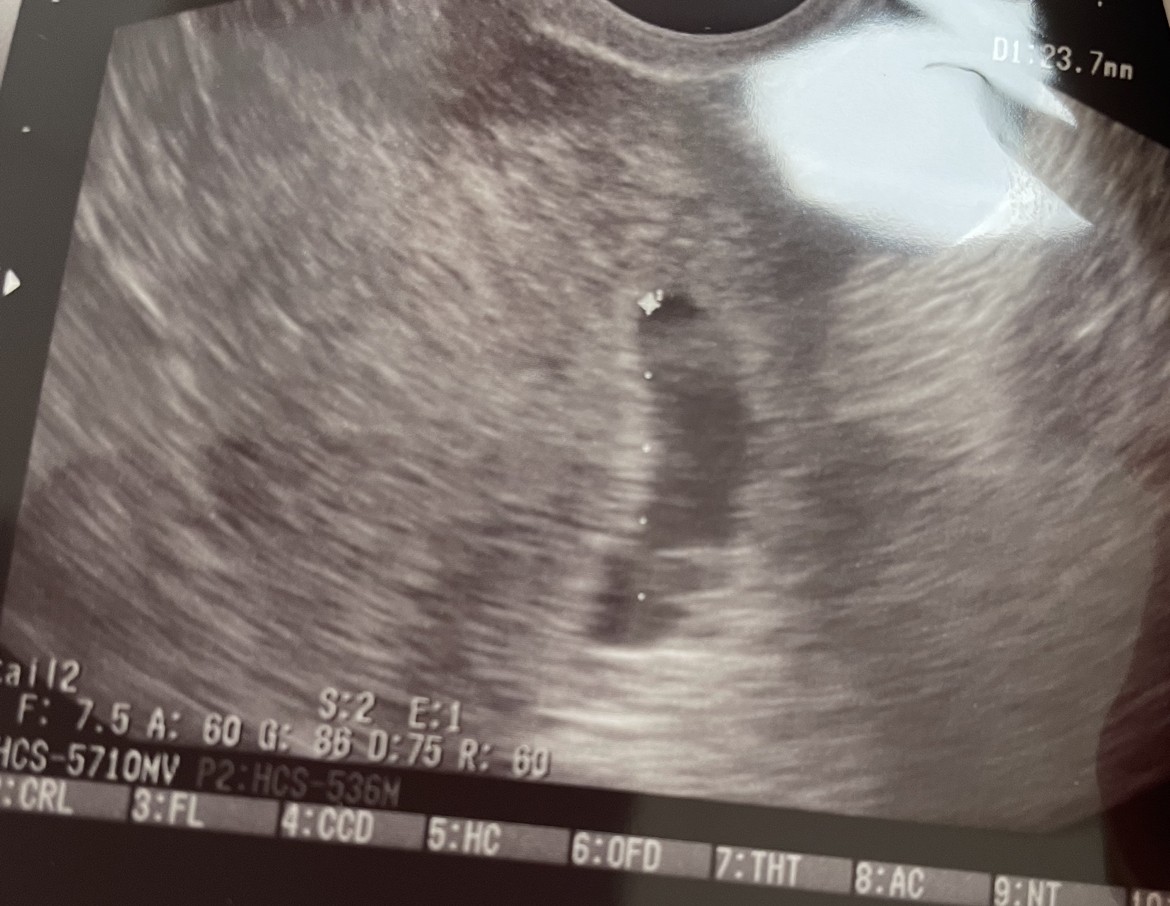

Pielęgniarka w szoku, że nie dał mi zdjęcia… opisu w karcie nie było. Badania z krwi są w porządku, beta z poniedziałku 115037. Pęcherzyk ciążowy na wizycie 7+4 miał 23 mm, spłaszczony, bez widocznego zarodka.Albo bym się przeszła do pielęgniarek zobaczyć swoje USG w karcie i co tam zapisał.

Nie wiem co Ci powiedziećPielęgniarka w szoku, że nie dał mi zdjęcia… opisu w karcie nie było. Badania z krwi są w porządku, beta z poniedziałku 115037. Pęcherzyk ciążowy na wizycie 7+4 miał 23 mm, spłaszczony, bez widocznego zarodka.Zobacz załącznik 1669836

Pęcherzyk już spory ,niestety brak zarodkaPielęgniarka w szoku, że nie dał mi zdjęcia… opisu w karcie nie było. Badania z krwi są w porządku, beta z poniedziałku 115037. Pęcherzyk ciążowy na wizycie 7+4 miał 23 mm, spłaszczony, bez widocznego zarodka.Zobacz załącznik 1669836

Pęcherzyka żółtkowego też nie ma?Pielęgniarka w szoku, że nie dał mi zdjęcia… opisu w karcie nie było. Badania z krwi są w porządku, beta z poniedziałku 115037. Pęcherzyk ciążowy na wizycie 7+4 miał 23 mm, spłaszczony, bez widocznego zarodka.Zobacz załącznik 1669836